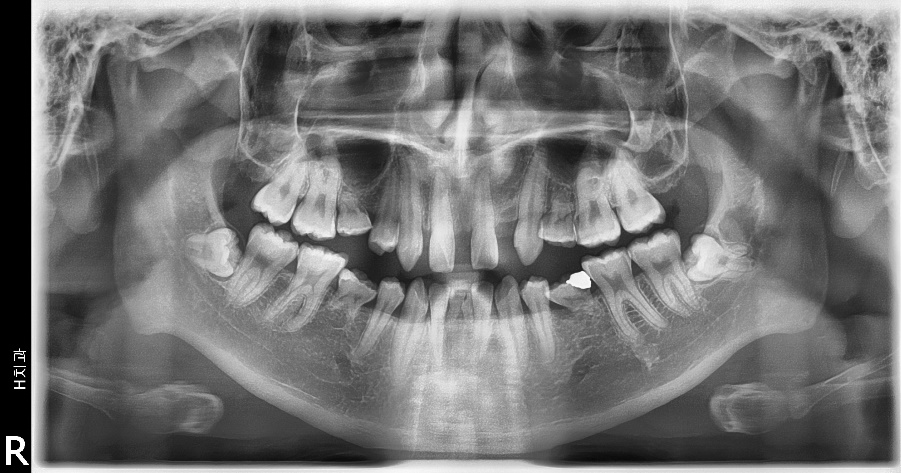

이 환자는 상악 양측 측절치와 양측 제1, 2 소구치, 하악 양측 제1, 2소구치, 양측 중절치의 결손을 가진 multiple congenital missing 환자입니다만 계속적 권유에도 불구하고 임플란트를 통한 전치부의 spacing 해결만을 원하였습니다.

때문에 상악에서만 부분교정을 통해 측절치 임플란트 식립 공간을 확보하기로 하였으며 동시에 상악 중절치의 반대교합 수정을 하기로 하였습니다.

일반적인 상악 측절치의 경우 전후방적 공간은 평균 6.5미리로 적정 임플란트의 직 경은 3.5미리가 적절하지만 위 증례의 경우 7.5미리를 교정원장님께서 확보해 주셨기 때문에 사용한 임플란트의 직경은 4.0미리를 사용하였습니다.

물론 그에 따른 순측골의 두께가 얇아질 수 있기 때문에 limited flap(Hincision)을 통 한 GBR(xenograft+resorbable membrane)을 시행하였습니다.

임플란트 보철치료가 완료된 후 생길 수 있는 잔여접촉점 사이의 공간 폐쇄를 위해 다시 교정의에게 의뢰하였습니다. 선천적 결손 부위인 하악 양측 제2소구치의 경우 하방의 골밀도는 일반적으로 떨어져 있는 경우가 많습니다.

초기 2.0/2.1/2.2의 드릴링 시에 골밀도를 정확히 체크하여 optimal underdrilling을 고려해야만 예지성있는 초기고정을 얻어낼 수 있고 또한 하방의 이공(mental foramen) 위치를 인지하며 수술을 해야 합니다.

하악전치의 경우 전후방적 공간은 5 미리내 외이므로 onebody implant, 필자는 이번 경우 덴티스의 I fix 2.5X13mm를 사용하였고 큰 무리 없이 임플란트 보철까지 완료하였습니다.